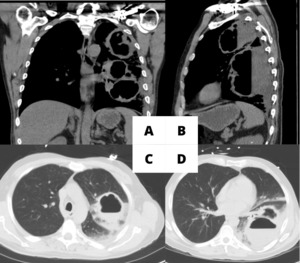

A 53-year-old male with a 35 pack-year smoking history, and alcohol use disorder, who presented with emesis and productive cough with dark colored sputum. On admission, the patient had a heart rate of 103 beats per minute. The respiratory clinical exam showed coarse upper airway sounds. C-reactive protein level was 325.2 mg/L and white blood count (WBC) was 20,000 upon admission. The chest computerized tomography (CT) showed two large lung abscesses with nodularity in the walls of the lung abscesses (Figure 1).

The patient was managed with levofloxacin and metronidazole for two weeks after the placement of drains, with the plan of continuing 4 more weeks of oral therapy after removal of the drains. Placement of drains resulted in a significant reduction (>50%) in the size of the cavities (Figure 2-B & Figure 3). CRP normalized to 1.3 mg/L and WBC was 4,000 at the time of discharge, with complete resolution of pulmonary symptoms.